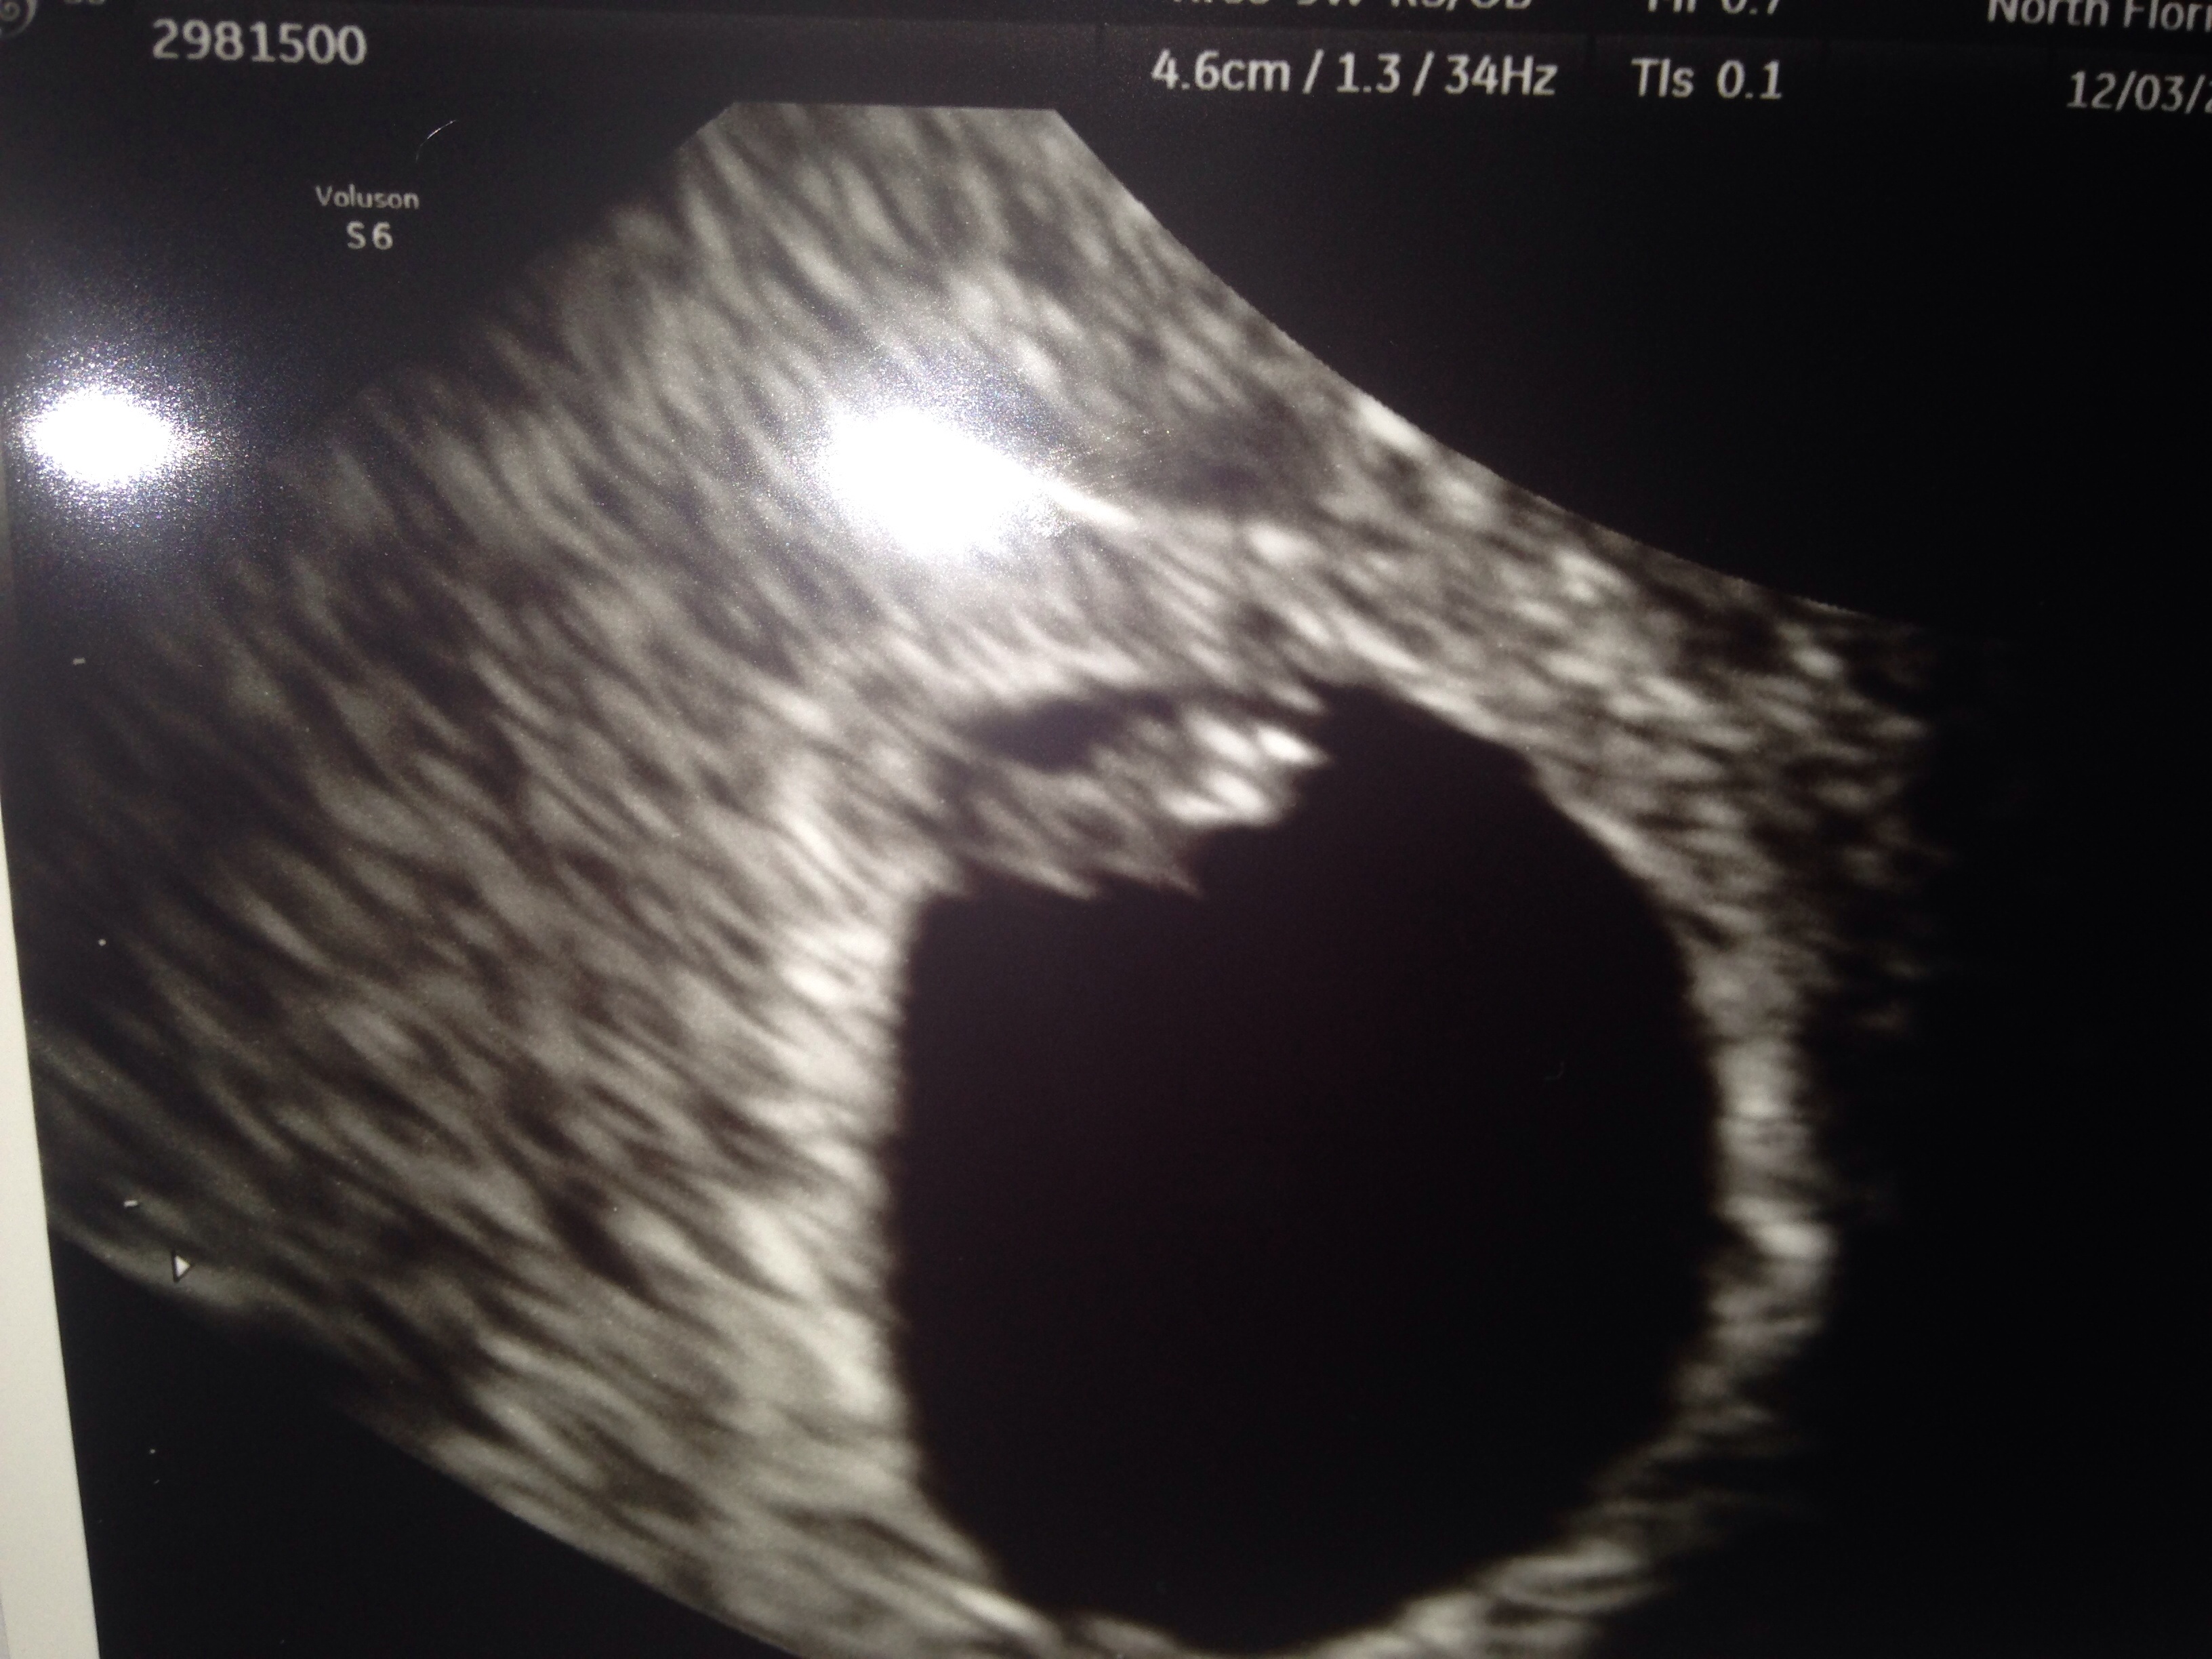

Hello ladies can someone please look at my ultrasound and tell me what u think the gender is based on ramzi theory? It was right with my last baby please!!! This is transvaginal at 6w3d and hr is 134